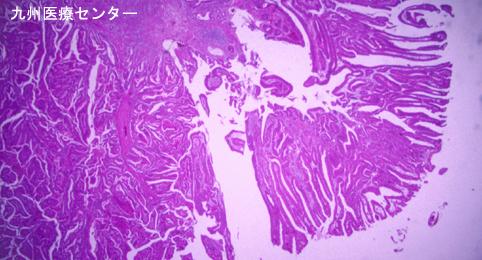

질환(병리주체)의 분류 악성 상피성종양/선암

부위(장기별) 십이지장/하행각

검사방법 마이크로

종양의 육안분류 0형(표재형)/I형(Ip)

종양의 최대경(밀리미터) 25~29

종양의 심달도 sm